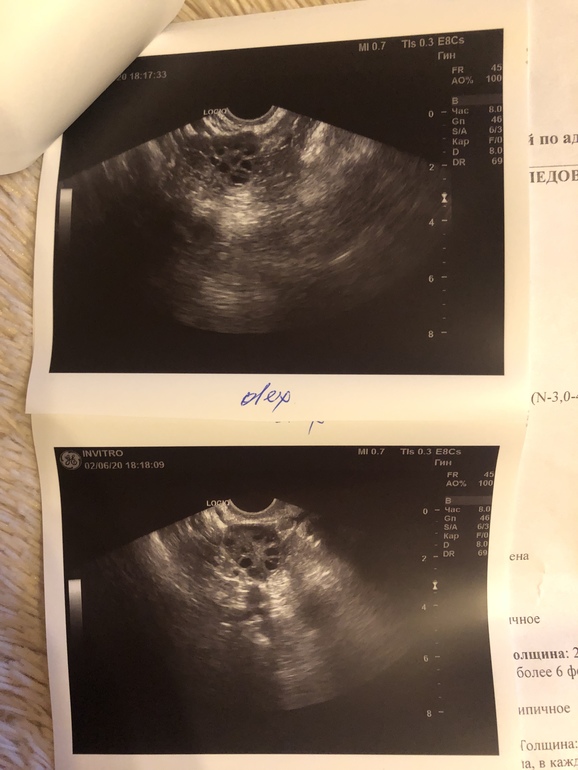

Пришла на узи на 25 дц, чтобы узнать, была ли овуляция в этом цикле. Цикл 28 дней. Регулярный, но болезненный.

Врач сказала, что в правом точно овуляции не было, а левый она не смогла разглядеть. Возможно, желтое тело превратилось в белое, или овуляции не было вообще. Так же сказала, что яичники мульфолликулярные, что, возможно, вообще в этом цикле не созревали. МФЯ страшно?

Про эндометрий ничего не сказала, но он тонкий, как я понимаю. это нормально для этого дц?